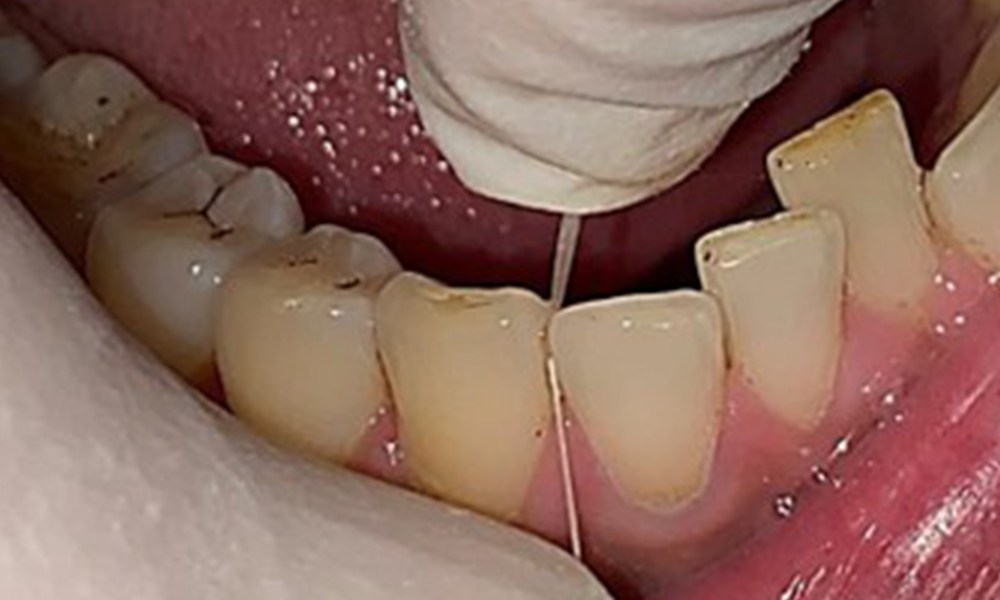

Close-up view of teeth

Fig. 5: Close-up view of teeth 45 to 47. The green arrows show dental attrition and erosions of the buccal cusps with partial enamel loss, © Dr R. Krapf

Dental findings

The patient has full dentition with a total of 28 teeth. There were noteworthy erosions and attritions. (Fig. 4, Fig. 5). Due to bruxism, the patient has been wearing a splint with an adjusted bite block at night for many years. The erosions were caused by long-term consumption of isotonic beverages. No periodontal bone loss or active caries were observed.